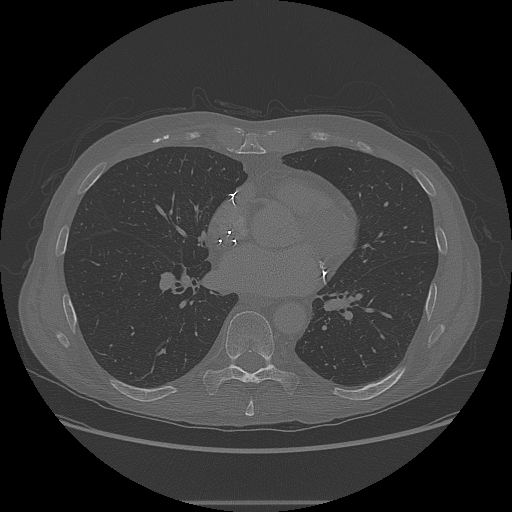

Просмотрите 2D срезы с помощью imshow функция.

figure imshow(XY,[],'Border','tight');

imshow(XZ,[],'Border','tight');